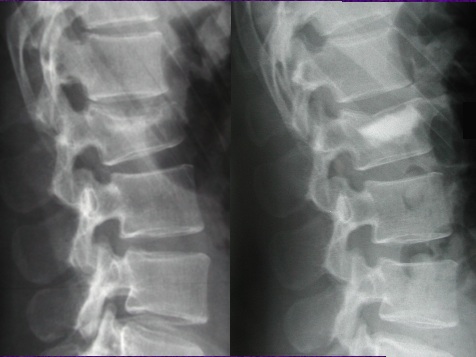

A la izquierda vemos el aspecto de una fractura L1. A la derecha, la misma lesion una vez reparada mediante cifoplastia con calcibon. Notese como se ha logrado remodelar la apariencia acu;ada de la vertebra a una morfologia casi normal. La densidad blanca dentro del cuerpo vertebral corresponde al material inyectado en el hueco abierto por los balones.